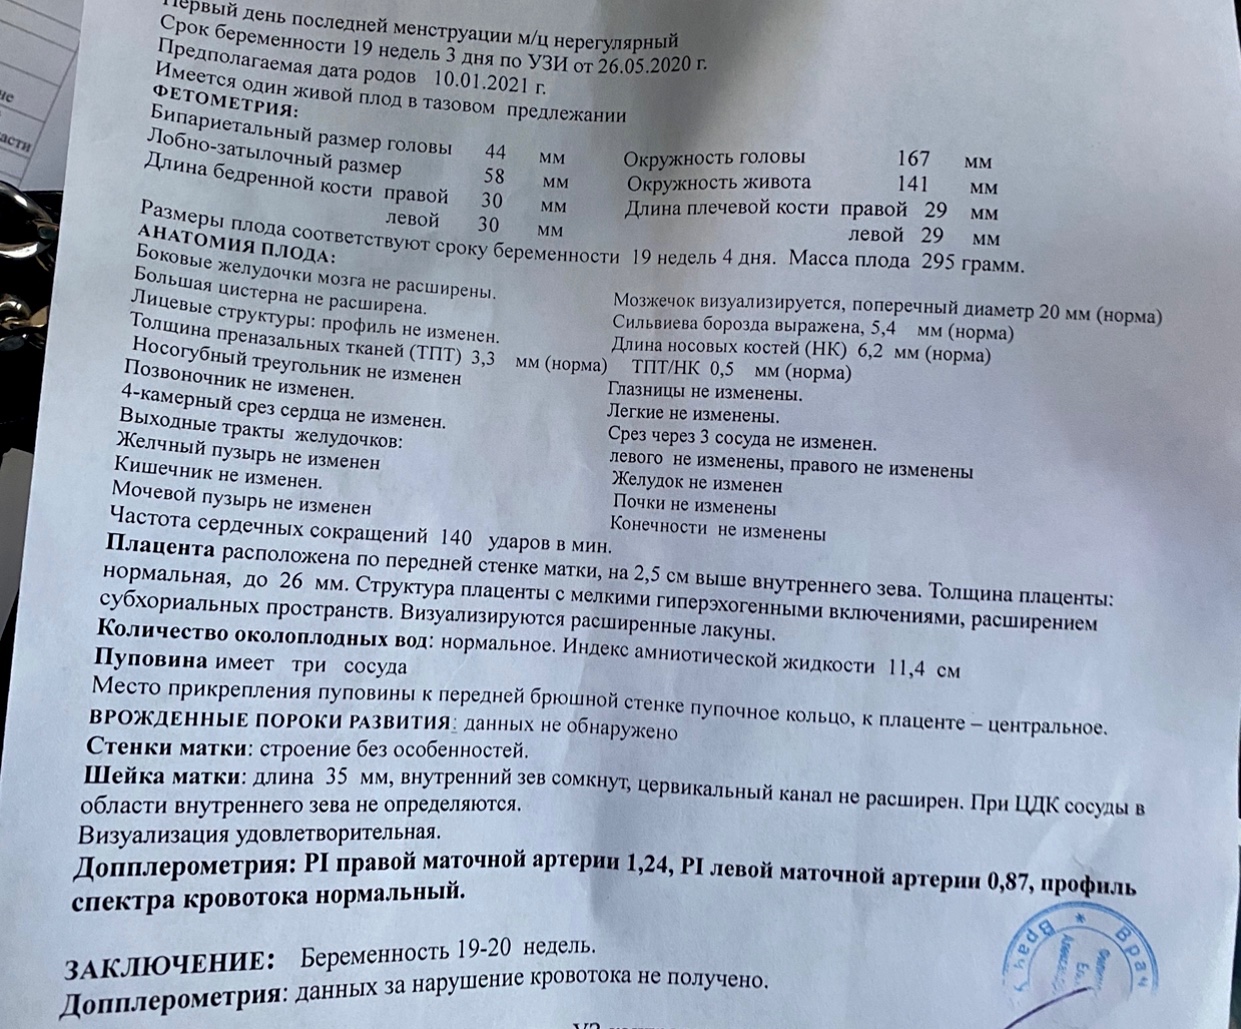

Важный этап: развитие малыша на 20-й неделе беременности